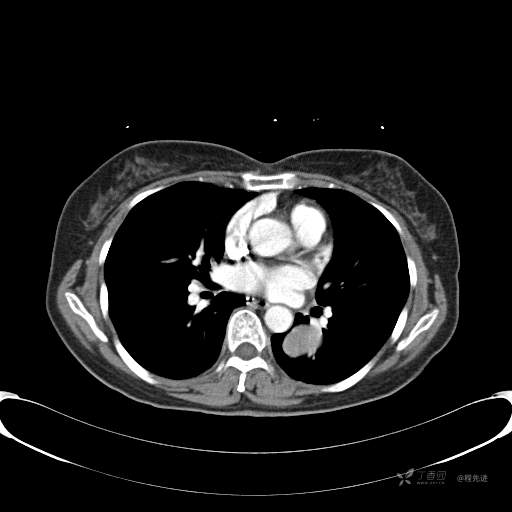

6月特别精彩病例|中老年女性,体检发现左肺下叶肿块,期待你的精彩演绎【病理公布】

患者性别:女

患者年龄:57岁

简要病史:体检发现

CT增强

平扫CT值约40HU(未上传图像),增强后动脉期CT值约70HU,静脉期CT值约97HU。

肺硬化性血管瘤 (20)